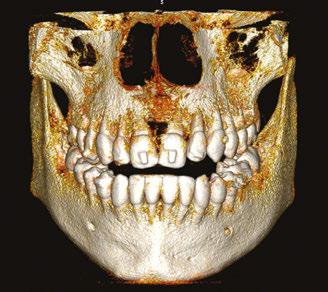

Drs. Claudia Pinter and Stanley Liu illustrate a protocol to improve nasal breathing in orthodontic care 31